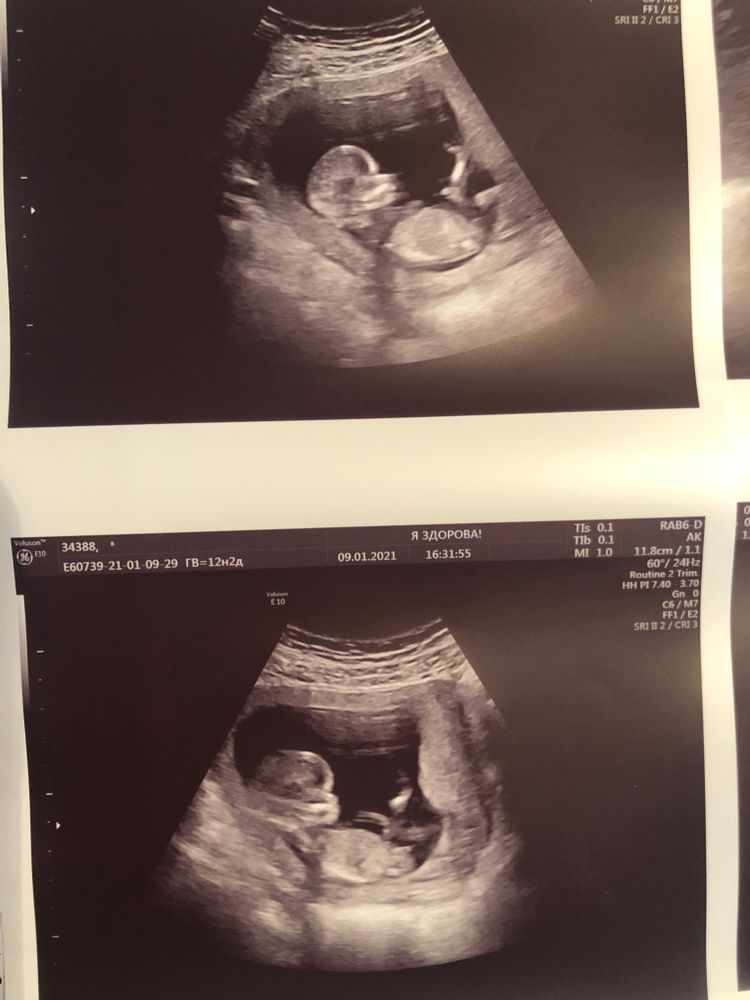

Первый скрининг мальчик или девочка?😍

Такой малышуля забавный, 🥰🥰🥰❤ больше на девочку похоже)